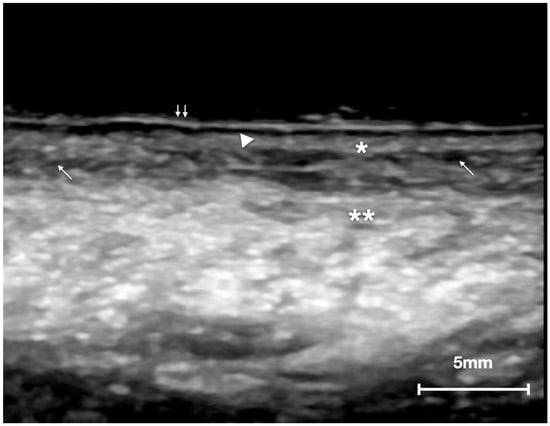

3.1. Healthy Tongue Features

- (a)

- A well-defined continuous hyperechoic band that corresponded to the epithelial layer.

- (b)

- An anechoic line with a thickness similar to the epithelium above, representing the short, blunt rete ridges. This layer consisted of the oral mucosa limit since it is impossible to identify the basement membrane for resolution limits of all ultrasound equipment (even at higher frequencies).

- (c)

- A homogeneous, relatively hypoechoic band of connective tissue, where submucosa merged and intersected with the ventral muscle bundles of the tongue.

- (d)

- An alternation of hypoechogenic, hyperechoic, and anechoic areas configuring striated muscle bundles that recall the histological fascicular features. A very slight acoustic enhancement was present. This layer represented the thickest portion of the ultrasound image, and within this area, it was also possible to observe the vessels of medium and large caliber.